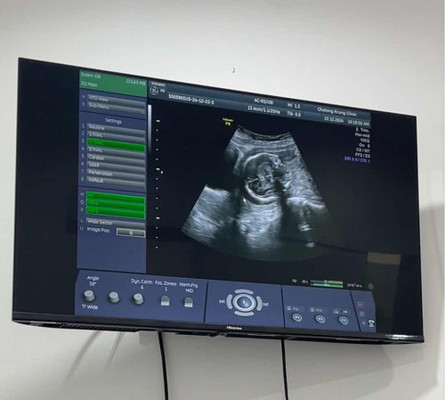

21W น้องเอาหัวลงต่ำ เสี่ยงคลอดก่อนกำหนด จากในภาพคือหัวน้องเบียดอยู่กับกระเพาะปัสสาวะ แถวๆลูกศรชี้คือปากมดลูก หมอจ่ายยากันแท้งมาให้เหน็บ 14วัน แล้วนัดไปดูอีกทีว่าเหน็บยาแล้วเป็นยังไง ถ้ายังเสี่ยงสูงอยู่หมอจะพิจารณาให้หยุดงานแล้วนอนพักอยู่บ้านค่ะ แม่ท่านไหนเคยเจอแบบนี้บ้าง น้องมีโอกาสจะเอาหัวขึ้นอีกมั้ยคะ หรือทำได้แค่ประคับประคองน้องไว้ให้ได้นานที่สุด ตอนนี้กังวลมากๆค่ะ 🥺